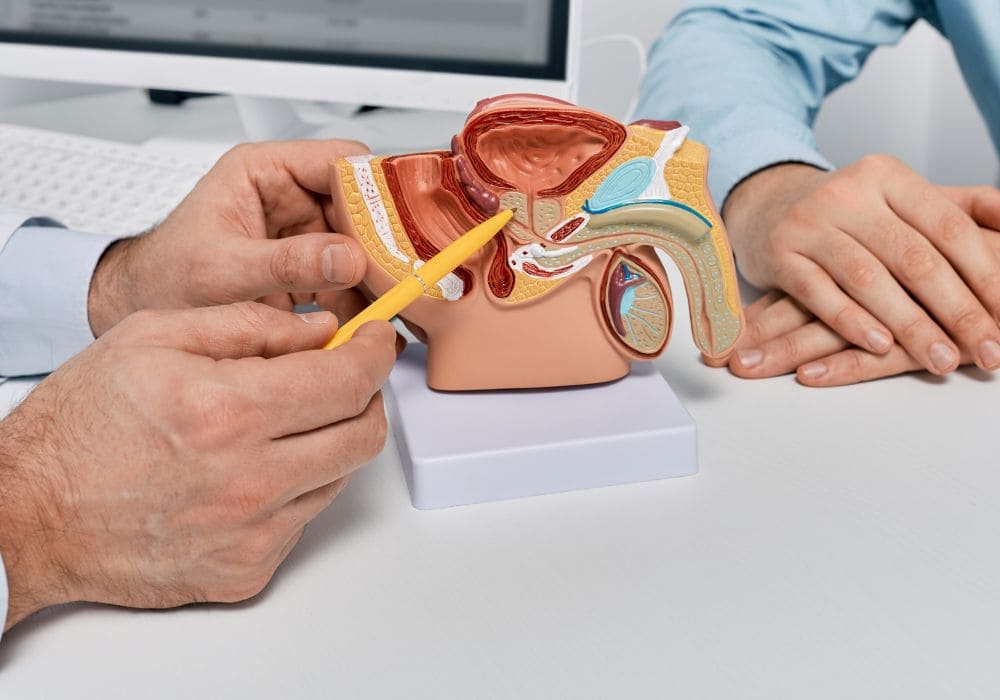

Entendendo a Próstata e seus problemas

O que é a próstata e para que serve? A próstata é uma glândula pequena, do tamanho de uma noz, que fica na pelve dos homens, logo abaixo da bexiga e na frente do reto. Ela envolve a parte inicial da uretra, que é o tubo que leva a urina da bexiga para fora do